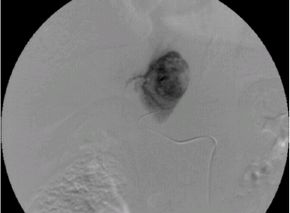

子宮筋腫に対する子宮動脈塞栓術(UAE)の実際

子宮動脈塞栓術(UAE)とは、子宮筋腫に栄養を与えている子宮動脈の血流を止めること

によって、筋腫を縮小させ、筋腫によって生じる過多月経などの症状を改善する治療法

です。足のつけ根に局所麻酔を行い、足のつけ根の動脈にカテーテルを入れ筋腫の近く

まで進めます。カテーテルから塞栓物質を注入し、血管を塞ぎ血流を止めます。塞栓が

完了したらカテーテルを抜き、傷口を押さえて止血します。

血管描出(塞栓前) 血管描出(塞栓後)